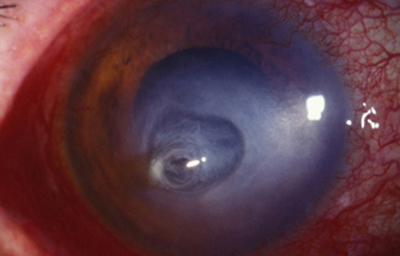

Superficie corneal irregular y grisácea, (Fig. 1, 2) con opácidades granulares en parche y formación de líneas epiteliales elevadas de aspecto granular (Fig. 3), que pueden arborizar dando imágenes de pseudodendritas. Opacidades superficiales satélites. (Figura 4) Inyección ciliar. Ulceración epitelial variante. (Figura 5).

Fig. 1 Síntomas de 15 días evolución

Fig. 2 Síntomas de 25 días evolución